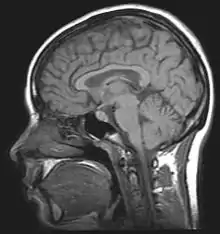

Magnetic Resonance Imaging creates images from the magnetic behaviour of hydrogen protons in brain tissue, and so can show more detail (down to around 1mm) than Computed Tomography. These imaging methods are mainly used to investigate anatomical structures and the processes associated with disease, not the dynamic functioning of the brain.